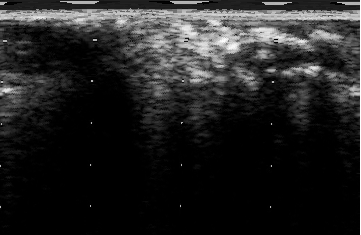

Segmentation of the acquired IVUS images is among the most challenging tasks in medical image analysis. In particular, delineating the interior (lumen) and exterior (media) vessel walls is problematic due to the presence of various artifacts such as motion of the catheter after a heart contraction, guide wire effects, bifurcation and side-branches or similar echogenicity between the vessel wall and some plaques. In some cases even the difference in transducer frequencies affect the segmentation results [2].

The intrinsic difficulty of IVUS segmentation has attracted many researchers to study and develop solutions using different methodologies, such as intensity-based, statistics and probability-based, active contour and graph search-based approaches. In addition, several methods have been proposed to segment either the lumen or the media or both. A great number of approaches in the literature have utilized the 2D information provided as cross-sectional frames to segment the lumen and media. These 2D cross-sectional gray-scale images are formed after digitization of the backscattered RF signals and are called IVUS B-mode frames. To the best of our knowledge, recent approaches have mostly worked on the B-mode frames which will be reviewed in the following paragraph. For more in-depth reviews of the methods published before 2013, please refer to [2, 4].